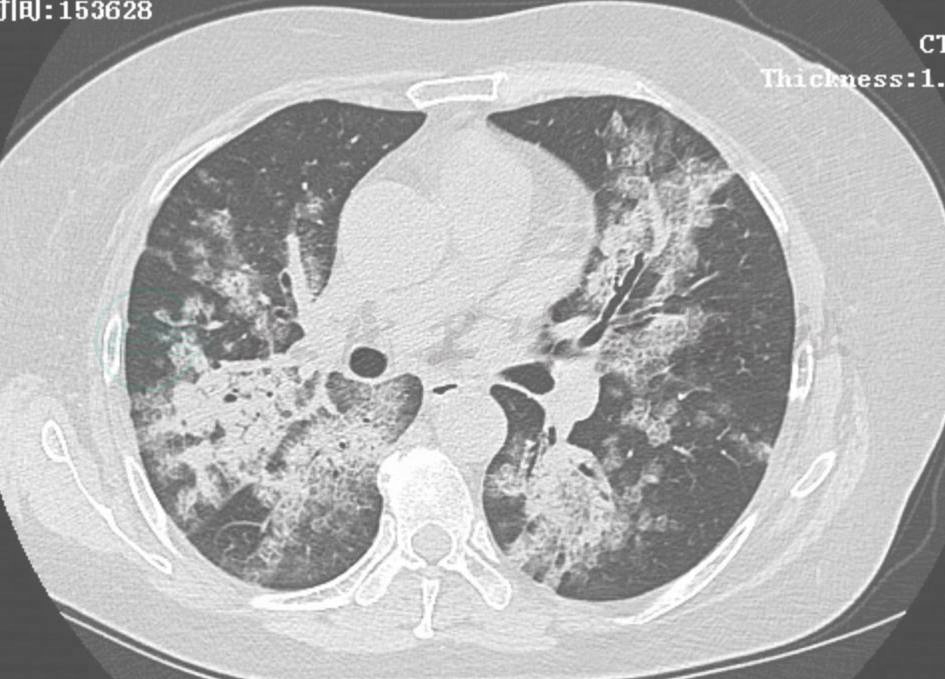

HRCT检查提示弥漫性簇性微结节聚集征以及广泛树芽征,呈地图状分布,纵隔淋巴结肿大 (图1)。

图1 不同病程阶段胸部HRCT表现

HRCT可见双肺弥漫性簇性微结节聚集征以及广泛树芽征,呈地图状分布(A),纵隔淋巴结肿大(B),并且随病程延长(10个月后)肺内类似病变有增多趋势(C)